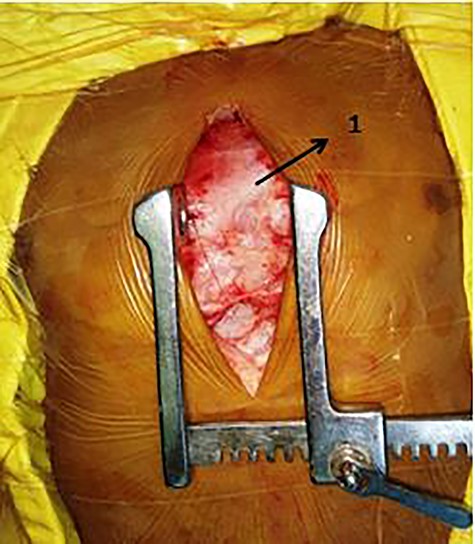

A 7-year-old male child got admitted to pediatric emergency ward with symptoms of breathlessness since 3 days. He was emaciated, febrile, pale, engorged neck veins, ascites with tensed abdomen without any pedal edema. Chest auscultation revealed diminished breath sounds on left side of the chest with muffled heart sounds. He was on drugs for abdominal tuberculosis for the last 2 months. A chest X-ray revealed left-sided pleural effusion, few calcific nodules on left hilar region with calcific heart borders. Ascitic fluid tap was done and around 2 l of amber colored fluid was drained out. The sample had raised adenosine deaminase level without any mycobacterium on routine examination of the centrifuged sample of the fluid. An urgent transthoracic echocardiography (TTE) was done, which revealed thickened pericardium, paradoxical movement of interatrial septum and hepatic flow reversal of blood during cardiac cycle suggesting constrictive pericarditis. Contrast-enhanced computer tomography (CECT) of thorax revealed thickened calcified pericardium with left-sided pleural effusion. The child was planned for anterior pericardiotomy next morning following routine work-up. Preoperative transesophageal echocardiography (TEE) on operation table showed an echogenic mass in right atrium, suggesting huge thrombus that was not detected on echocardiogram as well as on CECT. Hence, a plan to consider anterior pericardiectomy with the aid of cardiopulmonary bypass was made to remove thrombus from the right atrium. The anterior pericardium was very thick, whitish and glistening, suggesting a long-standing pathology (Fig. 1). Anterior pericardiectomy extending from just below the course of innominate vein till its joining the diaphragm and bilaterally limited till the phrenic nerves was performed. The operation was uneventful with satisfactory postoperative outcome and smooth recovery. He is on follow-up for the last 2 years without any symptoms of breathlessness or ascites.

Intraoperative picture of thickened pericardium (1—thick, whitish and glistening anterior pericardium).